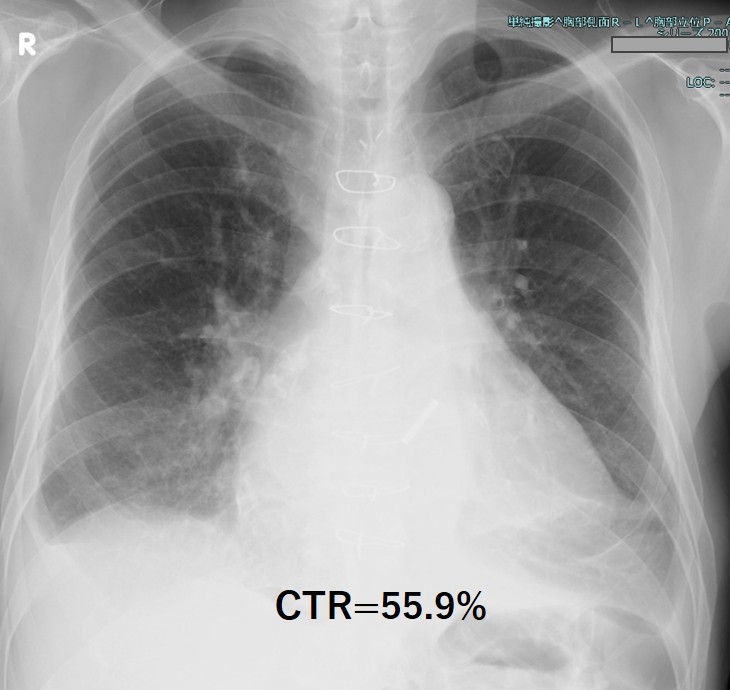

70 years old male with dyspnea on effort wasintroduced to our center for percutaneous ventricular septal perforation (VSP)closure. His past history revealed aortic valve replacement(AVR) 16 years agoand recent re-do AVR with mechanical valve due to the paravalvular leakage (PVL).Heart failure symptom was NYHA class 3. The auscultation revealed holo-systolicmurmur 3/6 at the left sternal border and regurgitant murmur at the right side,and also significant bilateral pretibial edema.

Relevant Test Results Prior to Catheterization

Blood tests showed an increase in totalbilirubin to 5.0 mg/dl, along with an increase in LDH and decreases in Hb andhaptoglobin, indicating hemolytic anemia. NTproBNP also increased to over 3000.The transthoracic echocardiogram showed the VSP at the membranous septum nearthe aortic PVL, and also moderate tricuspid regurgitation. Aortogram and CTscan demonstrated the severe aortic PVL with interventricular left to right shuntnearby.